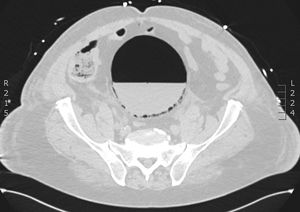

A 71-year-old male in the postoperative period of cardiac surgery presents with respiratory failure, severe hypoxemia, and predominantly left-sided subcutaneous emphysema, requiring re-intubation and 100% FiO2. A chest X-ray could not rule out bilateral pneumothorax. Additionally, he presents with significant hemodynamic instability requiring high doses of norepinephrine, and a distended, tympanic, and painful abdomen on examination, developing hyperlactacidemic acidosis. A CCTA performed confirms the presence of bilateral hydropneumothorax, mediastinal emphysema with involvement of the thoracic wall (Fig. 1), and at abdominal level, a distended bladder with a fluid-air level and atypical intraluminal air consistent with emphysematous cystitis of probable obstructive origin, with the Foley catheter distal end in the membranous urethra (Fig. 2). The Foley catheter was repositioned with the release of abundant gas, and a chest drain was placed. The patient showed progressive improvement with the resolution of emphysematous cystitis on follow-up CCTA.